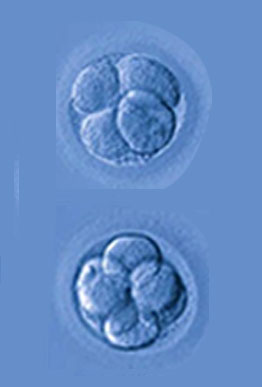

In vitro fertilisation is a process of fertilisation where an egg is combined with sperm in vitro.The process involves monitoring and stimulating a woman's ovulatory process.

In vitro fertilisation is a process of fertilisation where an egg is combined with sperm in vitro.The process involves monitoring and stimulating a woman's ovulatory process.

Intracytoplasmic Sperm Injection (ICSI) was pioneered by Van steirteghem and his team in Brussels and has revolutionized the management of male infertility.

Learn MoreWhen attempting to conceive a child, infertility issues are not always something that couples consider. However, around 20 to 30 percent of couples in the india face infertility issues. Among these issues is poor quality egg production by the female and sperm abnormalities with males,IVF Treatment in Ghatkopar.

Read MoreWhen attempting to conceive a child, infertility issues are not always something that couples consider. However, around 20 to 30 percent of couples in the india face infertility issues. Among these issues is poor quality egg production by the female and sperm abnormalities with males, ICSI Treatment in Ghatkopar.

Read MoreWhen attempting to conceive a child, infertility issues are not always something that couples consider. However, around 20 to 30 percent of couples in the india face infertility issues,ICSI treatment in Ghatkopar. Among these issues is poor quality egg production by the female and sperm abnormalities with males, ICSI treatment in Ghatkopar.